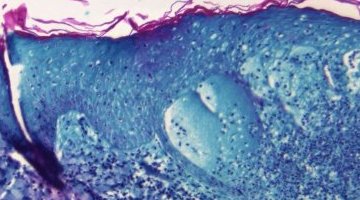

L’épidémie mondiale de choléra a explosé depuis le début de l’année. Avec 31 pays concernés dans ...

Environ la moitié des cas de choléra détectés à Haïti concernent des enfants, dont beaucoup sont ...

Une demande sera faite pour fournir à Haïti des vaccins oraux contre le choléra après le retour ...

La variole du singe a été classée en urgence de santé publique de portée internationale par le ...

Face à l’augmentation des cas de variole du singe, l’Agence sanitaire mondiale réunit ce jeudi ...